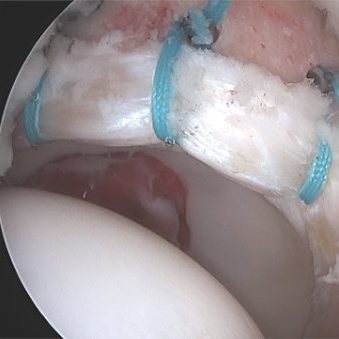

O mundo da ortopedia prepara-se para mais uma edição do 3.º HIP G.I.N. (Global Issue Network) Summit, um evento dedicado às grandes questões da cirurgia da anca. Organizado pelo Lusíadas Knowledge Center em parceria com a UpHill Events, o summit ocorrerá nos dias 21 e 22 de novembro de 2025, na Herdade da Comporta, reunindo…